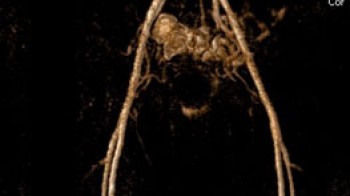

Vaskularni program (angiografije)

- MR angiografija glave

- MR venografija glave

- MR angiografija kičmene mozdine

- MR angiografija karotidnih arterija

- MR venografija vrata

- MR aortografija torakalne aorte

- MR aortografija abdominalne aorte

- MR angiografija perifernih krvnih sudova